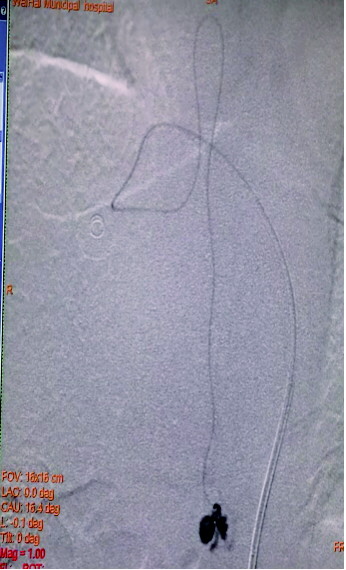

凭借精湛的技术,术中微导管精准地越过脊髓前动脉,为了保证手术的安全性,填入1×2、1×1、和1×1三个超软弹簧圈,造影显示瘘口闭塞,脊髓前动脉能清晰地显影,病变得到治愈。

图A为术前造影的正位图像,主供血为脊髓前动脉,引流静脉的起始部形成一个静脉球,远端呈迂曲状;图B为微导管到位后的超选造影,脊髓前动脉不显影(已越过);图C为栓塞结束后的造影,主供血的血流明显瘀滞,瘘口闭塞,下方的脊髓前动脉仍显影。